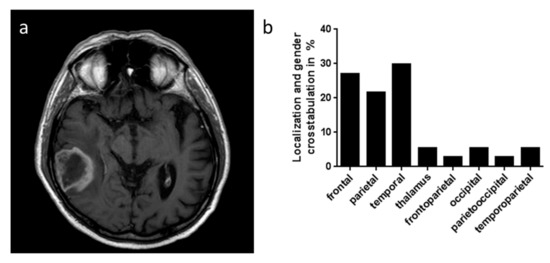

| Localization | ||||

| frontal | 5 | 5 | 10 | |

| parietal | 6 | 2 | 8 | |

| temporal | 9 | 2 | 11 | |

| thalamic | 2 | 0 | 2 | |

| fronto-parietal | 0 | 1 | 1 | |

| occipital | 2 | 0 | 2 | |

| perieto-occipital | 0 | 1 | 1 | |

| temporo-parietal | 2 | 0 | 2 | |